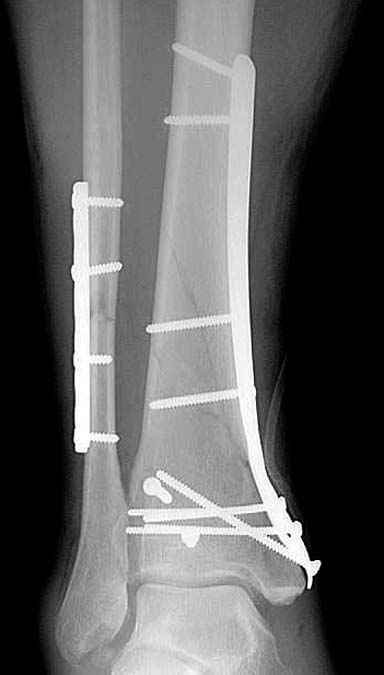

Спасибо за советы. Выполнен МОС обоих костей голени

Lig. tibiofibulare anterius оказалась целой. Был выявлен разрыв межкостной мембраны между берцовыми костями.

Разрыв межкостной мембраны между берцовыми костями был выявлен в зоне оперативного вмешвтельства на малоберцовой кости выше ее перелома. Логично было бы предположить, что он (разрыв) продолжается до проксимального синдесмоза голени. Но передняя межберцовая связка оказалась целой, поэтому ДМС оказался стабилен.

По представленным послеоперационным снимкам создаётся впечатление сохраняющегося подвывиха + итраоперационно обнаруженный разрыв межкостной мембраны.

Извините за некачественные снимки и неправильную укладку в прямой проэкции. Подвывих рентгенологически не определяется. Кроме этого, после МОС малоберцовой кости интраоперационно однозубым крючком проверена стабильность синдесмоза - он стабилен. Кроме этого, интраоперационно проверена стабильность стопы в голеностопе - люфта ее при боковых отклонениях не определяется, также визуально при этом приеме отклонения малоберцовой кости кнаружи в ДМС не определяется. В дополнение к этому (у ассистента были сомнения) был сделан доступ к межберцовой связке и ее визуальный осмотр- она оказалась целой. При данных обстоятельствах позиционный винт мы не вводим.

В обсуждаемом случае есть полный разрыв одной из важных составляющих дистального межберцового синдесмоза - межкостной мембраны. Зачастую при полном разрыве lig.tibiofibulare anterius после остеосинтеза лодыжки пластиной межкостная мембрана настолько прочно удерживает вилку сустава, что кроме шва дистального межберцового синдесмоза, введение позиционного винта не обязательно. Но в представленном случае разрыв межкостной мемраны особого значения не имеет, т.к. lig.tibiofibulare anterius цела. Поэтому ДМС поврежден частично, хотя практического значения это не имеет. Остеосинтез малоберцовой выполнен в большей мере потому, что пациент хотел обойтись без внешней иммобилизации.

Теперь о другом. Бережное отношение к тканям - это довольно философский вопрос. Есть мнения, что хорошей репозицией можно пренебречь, а главное - в меньшей мере травмировать надкостницу. Идеальная репозиция простого винтообразного перелома (студенческого) большеберцовой кости с скосом в 2,5 - 3 диаметра и МОС по правилам АО в сочетании с бережным (или не очень) отношением к надкостнице при отсутствии воспаления всегда (по моему опыту) приводит к консолидации в обычные сроки. До, можно было синтезировать и 3 - 5 винтами с чуть меньшего разреза (проксимальные 4 см пластины проведены под кожей), но все же это менее стабильно, чем МОС пластиной. Мне очень интересно понять Ваше мнение, какие детали послеоперационных рентгенограмм косвенно свидетельствуют об отношении хирурга к мягким тканям.